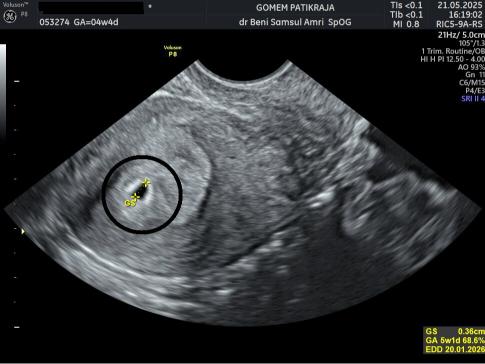

USG Janin 4 Minggu

USG pada trimester pertama (usia 8-12 minggu) dianggap paling akurat untuk menentukan usia janin dan mengoreksi HPL jika perlu.